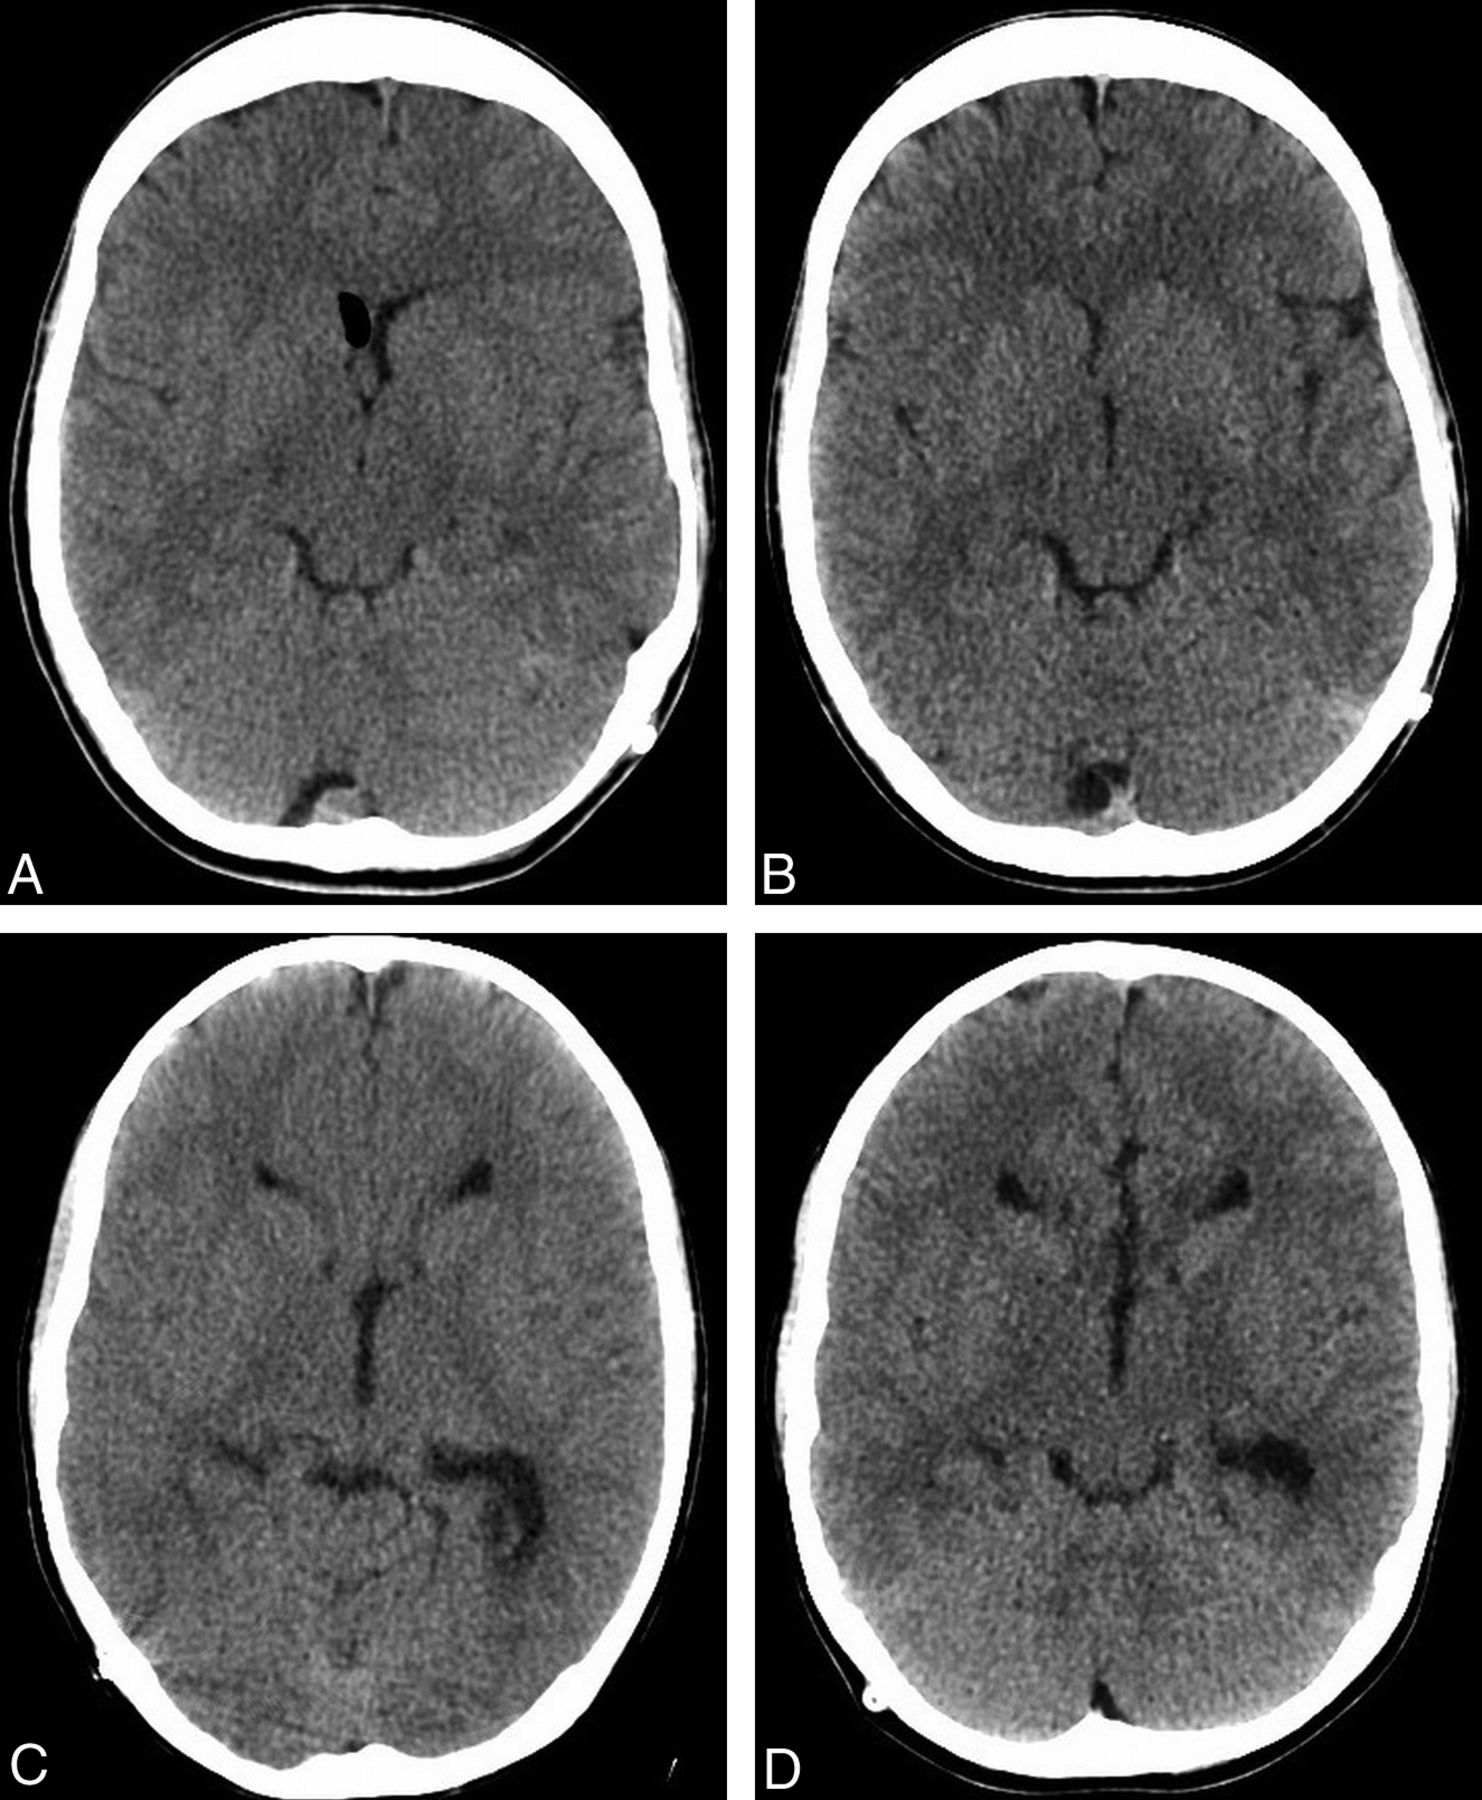

We found that CSF demonstrated significantly decreased noise in our ASIR examinations relative to our FBP examinations, while the other tested densities (WM, bone, air) did not demonstrate any significant noise differences between the 2 groups. This is similar to the findings of Kilic et al,21 which they attributed to the propensity of ASIR to disproportionately reduce noise in smoother areas.31 We also found that our subjective image scores for image artifacts tended to be lower in our ASIR examinations (Fig 5). This did not reach statistical significance, possibly resulting from our small patient sample. Prakash et al,12 however, did not note any improvement in the severity of windmill helical, beam-hardening, or metallic streak artifacts with the application of ASIR in their study comparing 156 patients who underwent abdominal CT reconstructed with ASIR against 66 different patients who underwent abdominal CT with FBP. One reason for these discordant findings could be that, unlike Prakash et al, we were able to directly compare the same reconstruction artifacts in the same patients. The effect of ASIR on reconstruction artifacts caused by high-attenuation objects, potentially relating to its smoothing effect, would be an interesting area of future research.

FBP (A) and ASIR (B) images through the level of the shunt reservoir in a 17-year-old boy, in which there are subjectively more reconstruction artifacts around the reservoir in the former study. The 2 examinations were performed 92 days apart, and the latter examination represented a 30.0% decrease in the CTDI (38.0–26.6 mGy) and a 27.5% decrease in the DLP (613.8–444.9 mGy-cm).